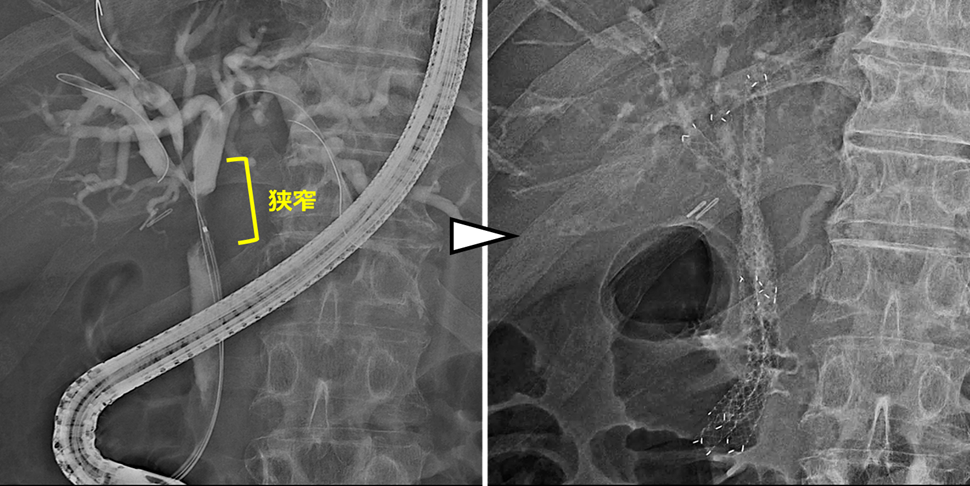

術後の良性胆管空腸吻合部狭窄に対する胆道ドレナージと拡張術

(十二指腸癌で膵頭十二指腸切除術、Child再建後)

膵頭十二指腸切除後に胆管空腸吻合部の狭窄を認めた症例です。

手術後1年が経過した頃に肝胆道系酵素の上昇を指摘され、内視鏡治療を行いました。胆管空腸吻合部に良性の狭窄を認めたため、狭窄部に対して金属ステントを交差するように留置しました。ステントは2~3か月程度留置した後に抜去することで、吻合部の狭窄は改善しました。

内視鏡治療後は肝胆道系酵素も改善し、その後は吻合部狭窄の再発も認めていません。